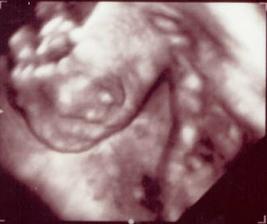

# 13.5. o 11.00 - 3D UTZ v stredisku Medifera v Aupark Tower, vzali nás presne načas. Babuľky na fóre odporúčali colu a čokoládu, aby bolo malé hore a malo veľa energie, tak som sa o desiatej prikŕmila dvoma riadkami čokolády (viac mi aj tak už nešlo) - a fungovalo to :D Keď sme sledovali nožičky, malé nimi trepotalo - hore, dole, pokrčiť, vystrieť - ale cez bruško som nič necítila na to, že toľko nacvičovalo. Rúčky malo najprv pred sebou potom sa škrabkalo na hlavičke... a ako typická baba - celý čas nezavrela pusu! Krásne bolo vidno celé telíčko, zvonka i zvnútra. Veľkosťou zodpovedáme ukončenému 20. týždňu gravidity a sme v poriadku - všetky orgány vyzerajú primerane a telesné proporcie tiež, nič nám nechýba. Pán doktor Holáň nám i nahlas pustil srdiečko - 153 tepov za minútu - nádherný rýchlik 🙂 Sme úplne šťastní a začíname vyberať meno 🙂 ...a aj výbavičku 🙂